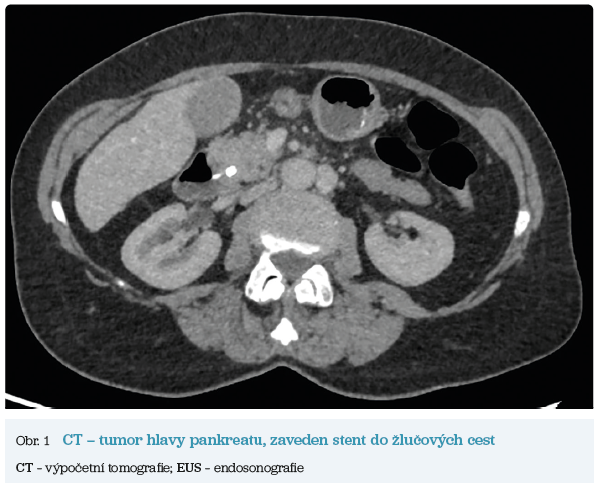

Několik studií se zabývalo AI asistovanou CT detekcí karcinomu pankreatu s AUC 0,79–0,99 %,6–8 tedy přesností porovnatelnou s přesností práce zkušeného radiologa. Stran časné detekce proběhla studie posuzující přesnost AI modelu v detekci karcinomu pankreatu v období 3–36 měsíců před prvními projevy onemocnění. Zařazeno bylo 155 pacientů s karcinomem pankreatu a 265 zdravých kontrol. AI model zde dosáhl AUC 0,98, což výrazně předčilo radiology, kteří při popisování stejných případů dosáhli AUC 0,66.9 Studie využívající DL model pro rozlišení zdravé slinivky od nálezu pankreatických neoplazií, tedy karcinomu pankreatu, intraduktální papilární mucinózní neoplazie (IPMN), serózních a mucinózních cystických neoplazií a solidní pseudopapilární neoplazie, byla prezentována s AUC 0,91, tedy opět odpovídající přesnosti popisu radiologa.10 Pro další vývoj a možné klinické využití bude potřeba přístupu k rozsáhlému archivu CT snímků karcinomu pankreatu, aby se ML modely mohly zdokonalovat. Další studie se věnovaly AI asistované diferenciální diagnostice. Ta bývá u lézí pankreatu velmi obtížná a pokrok v této problematice je tak velmi přínosný. Mezi nejzajímavější patří studie zabývající se rozlišením serózních a mucinózních cystadenomů s AUC 0,932.11 Další studie zkoumala úspěšnost rozlišení karcinomu pankreatu od zbytnění pankreatu při určitých formách chronické pankreatitidy (MFP – mass forming pancreatitis) s AUC 0,866.12 V další studii byla AI využita k rozlišení fokální autoimunitní pankreatitidy od karcinomu pankreatu s AUC 0,97.13 V rámci MR proběhlo několik studií, které se zaměřily na AI asistované zachycení a klasifikaci pankreatického karcinomu či IPMN. Studie klasifikující IPMN pomocí konvoluční neuronové sítě (CNN – convolutional neural network) byla schopna rozlišit dysplazii vysokého stupně od přítomnosti karcinomu se senzitivitou 76 %, specificitou 78 % a AUC 0,78.14 Další studie porovnávala AI modely CT a MR v predikci maligního IPMN. Výsledky ukázaly, že MR model s AUC 0,94 byl přesnější než CT model s AUC 0,864.15 S využitím PET/CT byl prozkoumán AI model rozlišující od sebe akutní pankreatitidu a karcinom pankreatu s AUC 0,9668.16 Výsledky AI v oblastech zobrazovacích metod jsou tak slibné. Dosahují minimálně přesnosti srovnatelné s radiologem a zejména v problematice časných karcinomů pankreatu člověka svojí přesností převyšují (obr. 1–5).

Vzhledem k výrazným pokrokům na poli hlubokého učení a zpracovávání dat získává AI možnost vést k transformaci klinické medicíny, jak ji známe. K lepší spolehlivosti AI také vede nárůst dostupných klinických dat, ze kterých se může učit. V rámci karcinomu slinivky břišní se další pokrok AI bude patrně zabývat časnou diagnostikou a predikcí nejefektivnějšího terapeutického postupu. Velký přínos se očekává zejména od hodnocení snímků zobrazovacích metod. Zde má velký vliv kvalita snímků a přítomnost abnormalit či jiných faktorů (například zavedených biliárních stentů), které mohou vést k nesprávným výsledkům. S nárůstem poznatků o karcinomu pankreatu bude zcela jistě růst i množství klinických dat a proměnných, proto i AI modely budou muset být vyvíjeny tak, aby zvládaly vyhodnocovat komplexní problematiku. Vzhledem k pokroku a mezioborové spolupráci bude AI zajisté velmi významným pomocníkem lékařů. Navzdory všem obtížím se tak AI patrně bude využívat ve všech aspektech problematiky karcinomu pankreatu (časná diagnostika, vymezení rizikových skupin, prognostický odhad, výběr nejlepšího terapeutického postupu, hodnocení efektu léčby).